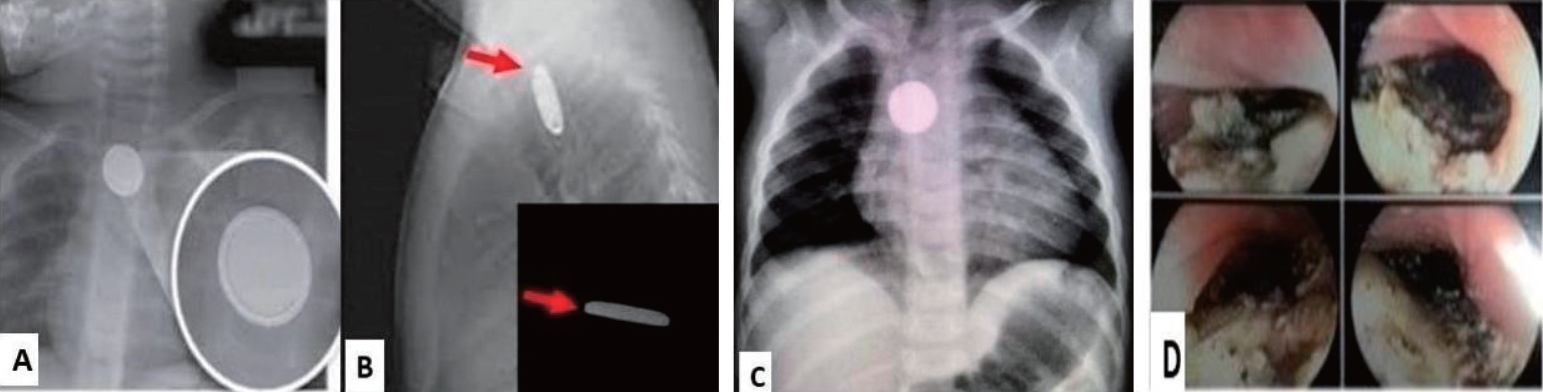

Fig. 3.

Differentiation between ingested coins and battery. (A) Double-halo sign. (B) Step-off sign (arrow). (C) Ingestion of battery. (D) Esophageal lesions and esophageal necrosis after battery ingestion.

2) Flat batteries

The consumption of flat batteries (Fig. 1B) has recently increased because of their widespread use in household appliances and other devices. Serious complications (esophageal burns, perforation, and/or fistula development) and/or death occur in 3% of battery ingestion cases [2,3,13]. Although disc-shaped batteries have been used for almost 30 years, their initial clinical experience with ingestion quite benign. Data collected and published by the National Capital Poison Centre in 1992 on >2,300 patients showed that over a 7-year period no deaths occurred and only 0.1% of affected individuals developed a serious complication consisting of 2 esophageal strictures [14]. However, over the next 20 years, clinical experience has changed dramatically with a new follow-up study from the same center. In this study of >8,600 cases, major complications occurred in 73 patients (0.8%), versus death in 13 patients (0.15%) [15]. The cause of this dramatic increase in morbidity and mortality appears to be linked to 2 specific changes in the market during this period: increased battery diameter and the change to lithium cells which cause an increased likelihood of esophageal impaction and increased pressure respectively. Lithium batteries >20 mm are responsible for 94% of battery ingestion-related deaths. The tissue damage is caused by the generation of hydroxide radicals; therefore, caustic mucosal damage is induced by from a high pH rather than electrothermal injury. Changes including, an increase in pH from 7 to 13 at the negative pole in 30 minutes and mucosal necrosis in 15 minutes [16] were observed in animal experiments.

These findings are compatible with reports of esophageal strictures at 2 hours after ingestion and highlighting the importance of immediate endoscopic interventions in these children.

Equally important is the distinction between circular foreign bodies in the esophagus, as batteries require immediate removal, whereas coins may not. For batteries, the double-halo or step-off sign Fig. 3 is characteristic. If simple radiographs cannot identify the foreign body, further investigation using computed tomography (CT) or noncontrast-enhanced magnetic resonance imaging (MRI) may be required especially if the patient is symptomatic or the foreign body has some dangerous characangiograteristics such as being sharp, long >5 cm. or large, (diameter >2 cm). If the patient is asymptomatic, the environment is reliable and safe for the ingested foreign body, and the object has benign characteristics, further imaging may not be necessary. The use of ultrasound to highlight a foreign body in the esophagus or stomach requires appropriate special operator experience [30]. Upper gastrointestinal transit with water-soluble contrast has been used to highlight mainly nonradioactive foreign bodies, whereas barium transit should be avoided since it may complicate localization of the foreign body during any upcoming gastroscopy.

6. Batteries